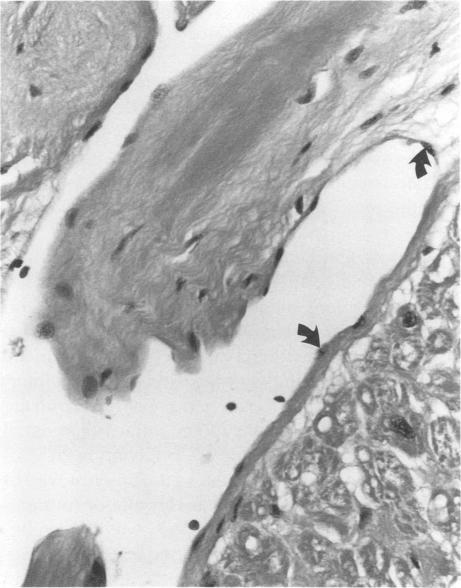

Papillary fibroelastoma. A right atrial presentation.

Papillary fibroelastoma is a rare cardiac tumor arising most frequently from valvular endocardium. These tumors are clinically important because of their tendency to embolize. Emphasis is therefore placed on early detection and surgical excision. We describe a case of a papillary fibroelastoma arising from the right atrium. To our knowledge, only 2 such cases have been reported in the English literature. Our case illustrates the discovery of a rare, but potentially fatal cardiac tumor, successfully removed by surgery.